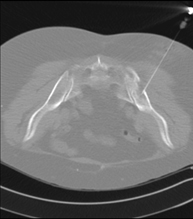

- PAAF (Punción) Tórax guiada por TC Prueba que consiste en obtener una muestra de tejido de lesiones torácicas, como por ejemplo masas pulmonares, mediastínicas, lesiones óseas, etc. Para ello se administra anestesia local sobre la zona de la punción, la cual se realiza con agujas de fino calibre. Todo el procedimiento se realiza controlado por imágenes obtenidas por Tomografía Computarizada (TC) en varios momentos de la punción, mediante un equipo de Fluoroscopia-TC. Tras la prueba, el paciente permanece unas horas hospitalizado. Es necesario aportar pruebas de coagulación antes de la punción. Prueba que consiste en obtener una muestra de tejido de lesiones torácicas, como por ejemplo masas pulmonares, mediastínicas, lesiones óseas, etc. Para ello se administra anestesia local sobre la zona de la punción, la cual se realiza con agujas de fino calibre. Todo el procedimiento se realiza controlado por imágenes obtenidas por Tomografía Computarizada (TC) en varios momentos de la punción, mediante un equipo de Fluoroscopia-TC. Tras la prueba, el paciente permanece unas horas hospitalizado. Es necesario aportar pruebas de coagulación antes de la punción.

- Biopsia tórax guiada por TC Consiste en obtener una muestra de tejido de una determinada lesión torácica, como por ejemplo del pulmón, del mediastino, del esternón, etc. A veces se realiza bajo sedación, con la ayuda del equipo de anestesia. Se utilizan agujas que permiten la obtención de un cilindro de la lesión a estudiar, que se enviará a Anatomía Patológica para su análisis histológico. Todo el procedimiento se realiza controlado con imágenes obtenidas por Tomografía Computarizada (TC) en varios momentos de la biopsia, mediante un equipo de Fluoroscopia-TC. Tras la prueba, el paciente permanece hospitalizado para controlar su evolución. Es necesario aportar pruebas de coagulación antes de la punción. Consiste en obtener una muestra de tejido de una determinada lesión torácica, como por ejemplo del pulmón, del mediastino, del esternón, etc. A veces se realiza bajo sedación, con la ayuda del equipo de anestesia. Se utilizan agujas que permiten la obtención de un cilindro de la lesión a estudiar, que se enviará a Anatomía Patológica para su análisis histológico. Todo el procedimiento se realiza controlado con imágenes obtenidas por Tomografía Computarizada (TC) en varios momentos de la biopsia, mediante un equipo de Fluoroscopia-TC. Tras la prueba, el paciente permanece hospitalizado para controlar su evolución. Es necesario aportar pruebas de coagulación antes de la punción.

- Intervencions guiades per TC- PAAF (Punció) de tòrax guiada per TC Prova que consisteix en obtenir una mostra de teixit de lesions toràciques, com per exemple masses pulmonars, mediastíniques, lesions òssies, etc. Per a tal s'administra anestèsia local sobre la zona de punció, que es realitza amb agulles de calibre fi. Tot el procediment es realitza controlat per imatges obtingudes per Tomografia Computaritzada (TC) en diversos moments de la punció mitjançant l'ús de Fluoroscòpia- TC. Després de la prova, el pacient resta unes hores hospitalitzat. És necessari que porti les proves de coagulació abans de la punció. Prova que consisteix en obtenir una mostra de teixit de lesions toràciques, com per exemple masses pulmonars, mediastíniques, lesions òssies, etc. Per a tal s'administra anestèsia local sobre la zona de punció, que es realitza amb agulles de calibre fi. Tot el procediment es realitza controlat per imatges obtingudes per Tomografia Computaritzada (TC) en diversos moments de la punció mitjançant l'ús de Fluoroscòpia- TC. Després de la prova, el pacient resta unes hores hospitalitzat. És necessari que porti les proves de coagulació abans de la punció.

- Biòpsia de tòrax guiada per TC Consisteix en obtenir una mostra de teixit d'una determinada lesió toràcica, com per exemple del pulmó, del mediastí, de l'estern, etc. A vegades es realitza sota sedació, amb l'ajuda de l'equip d'anestèsia. S'utilitzen agulles que permeten l'obtenció d'un cilindre de la lesió que s'ha d'estudiar, que s'enviarà a Anatomia Patològica per a la seva anàlisi histològica. Tot el procediment es realitza controlat per imatges obtingudes per Tomografia Computaritzada (TC) en diversos moments de la biòpsia mitjançant l'ús de Fluoroscòpia-TC. Després de la prova, el pacient resta hospitalitzat per controlar la seva evolució. És necessari que porti proves de coagulació abans de la punció. Consisteix en obtenir una mostra de teixit d'una determinada lesió toràcica, com per exemple del pulmó, del mediastí, de l'estern, etc. A vegades es realitza sota sedació, amb l'ajuda de l'equip d'anestèsia. S'utilitzen agulles que permeten l'obtenció d'un cilindre de la lesió que s'ha d'estudiar, que s'enviarà a Anatomia Patològica per a la seva anàlisi histològica. Tot el procediment es realitza controlat per imatges obtingudes per Tomografia Computaritzada (TC) en diversos moments de la biòpsia mitjançant l'ús de Fluoroscòpia-TC. Després de la prova, el pacient resta hospitalitzat per controlar la seva evolució. És necessari que porti proves de coagulació abans de la punció.